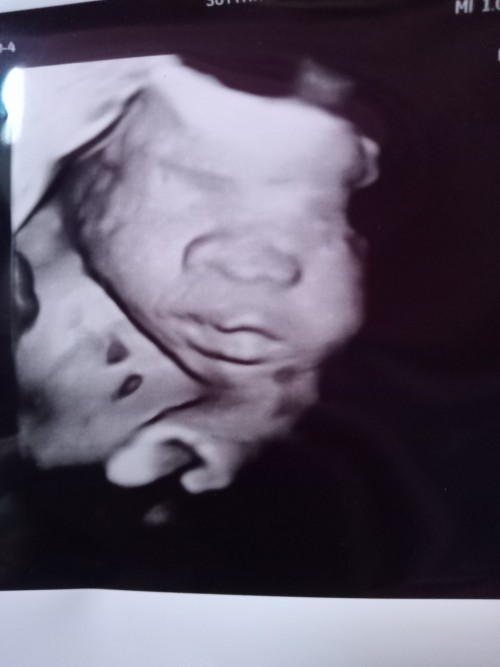

34+2วีคแล้วค่ะสาวอวบ🤣💓